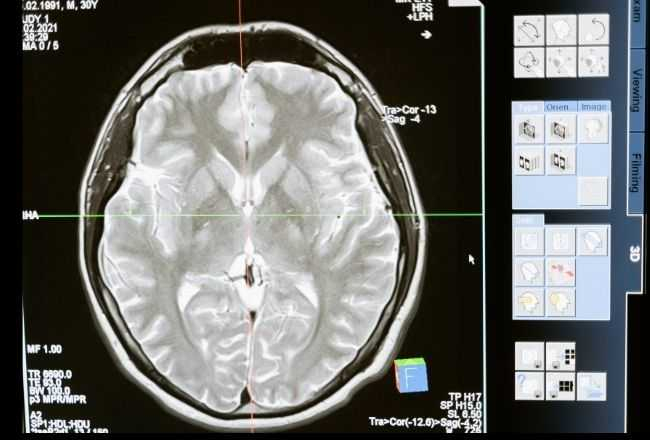

Rentgeno nuotraukos parodė, kad žaislinio automobilio ratas buvo įstrigęs labai arti mergaitės smegenų. Gydytojai iš pradžių bijojo, kad žaislas galėjo pažeisti smegenis.

Žaislo fragmentas vaiko galvoje. Kaip tai nutiko?

Laimei, Sperandskio vaikų ligoninės Nr.9 gydytojai nustatė, kad mergaitės smegenų paviršius nebuvo pažeistas, kai buvo atliekama įstrigusios žaislo dalies operacija.

„Turėjome įsitikinti, kad pažeistoje vietoje neliko jokių objekto dalių“, – sakė chirurgas Ruslanas Molotovas. Jis taip pat pabrėžė, kad dėl šio nelaimingo atsitikimo mergaitė nepatyrė jokios žalos, kuri galėtų pakenkti ateityje.